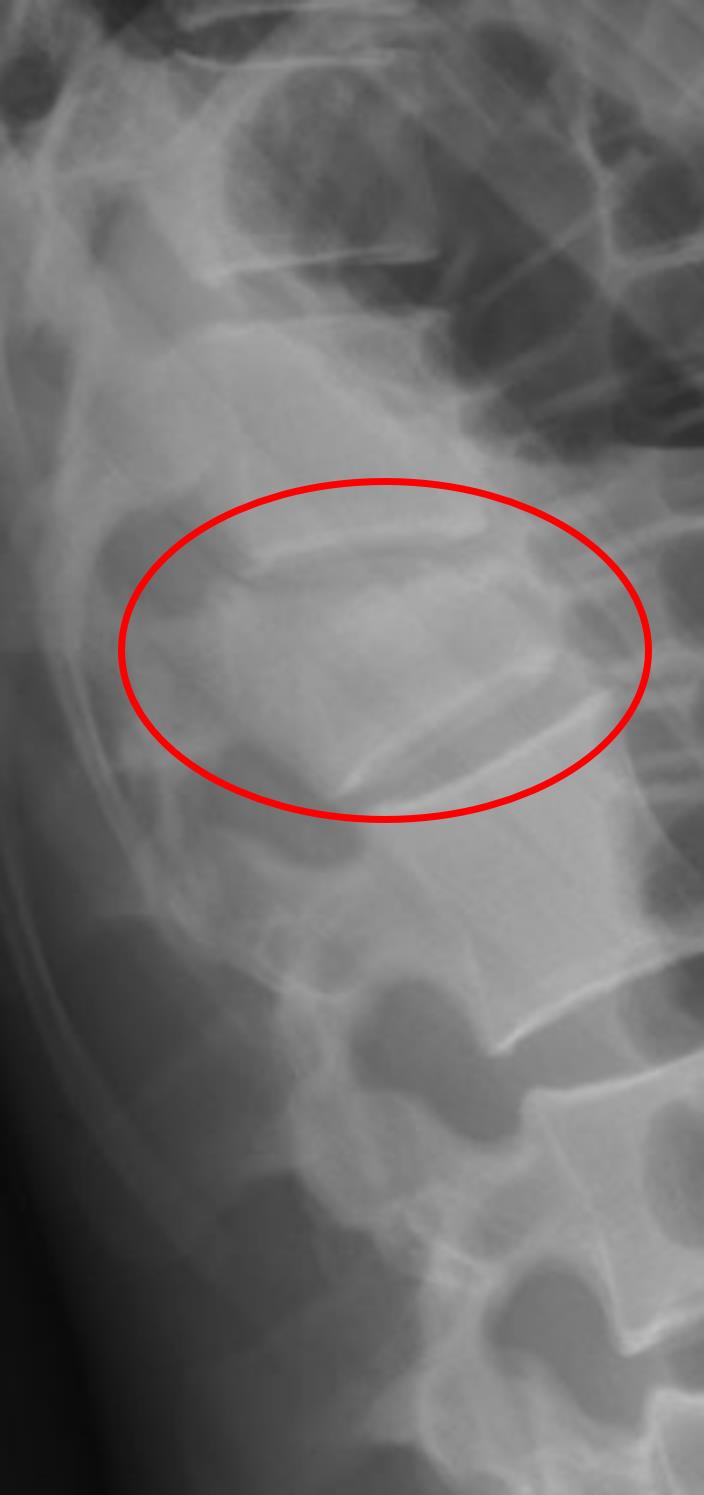

A 71-year-old woman presents to the emergency department with a 2 hour history of low back pain. She started experiencing the pain after waking up this morning but is not sure what triggered it. She does not usually get back pain and she has been feeling fine otherwise. Her medical history is significant for anxiety, HIV on antiretroviral therapy, and a 40 pack-year smoking history. Her temperature is 99.8°F (37.7°C), blood pressure is 147/98 mmHg, pulse is 100/min, respirations are 17/min, and oxygen saturation is 98% on room air. A physical exam is notable for tenderness to palpation over the patient’s midline spine. A radiograph is ordered, and the results are seen in Figure A. Laboratory values are ordered as seen below.

This patient, who presents with back pain and radiography with collapse of a vertebral segment and subsequent kyphosis, most likely sustained a low-energy vertebral compression fracture.

Figure/Illustration A is a radiograph demonstrating the collapse of the vertebral segment (red circle). This finding is consistent with a vertebral compression fracture.